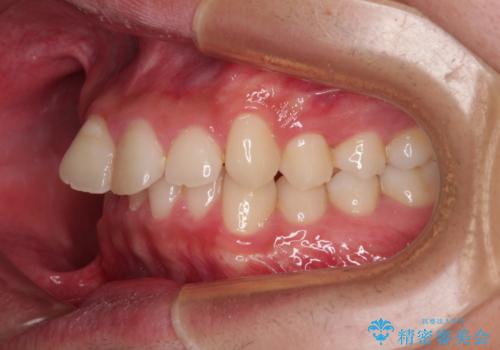

- ディープバイトと上顎前歯の突出、奥歯の咬み合わせを気にして来院された患者様です。

上顎歯列は全体的に前方位にあり、それが原因で深い咬み合わせとなり、突き上げにより上顎前歯が前方に飛び出している状態でした。

また、左右ともに上顎最後臼歯が頬側に転位している鋏状咬合となっていました。

補助装置を併用せずに治療を終える可能性はありましたが、確実に結果を得るために補助装置を活用しました。

イメージしたとおりの仕上がりとなりました。